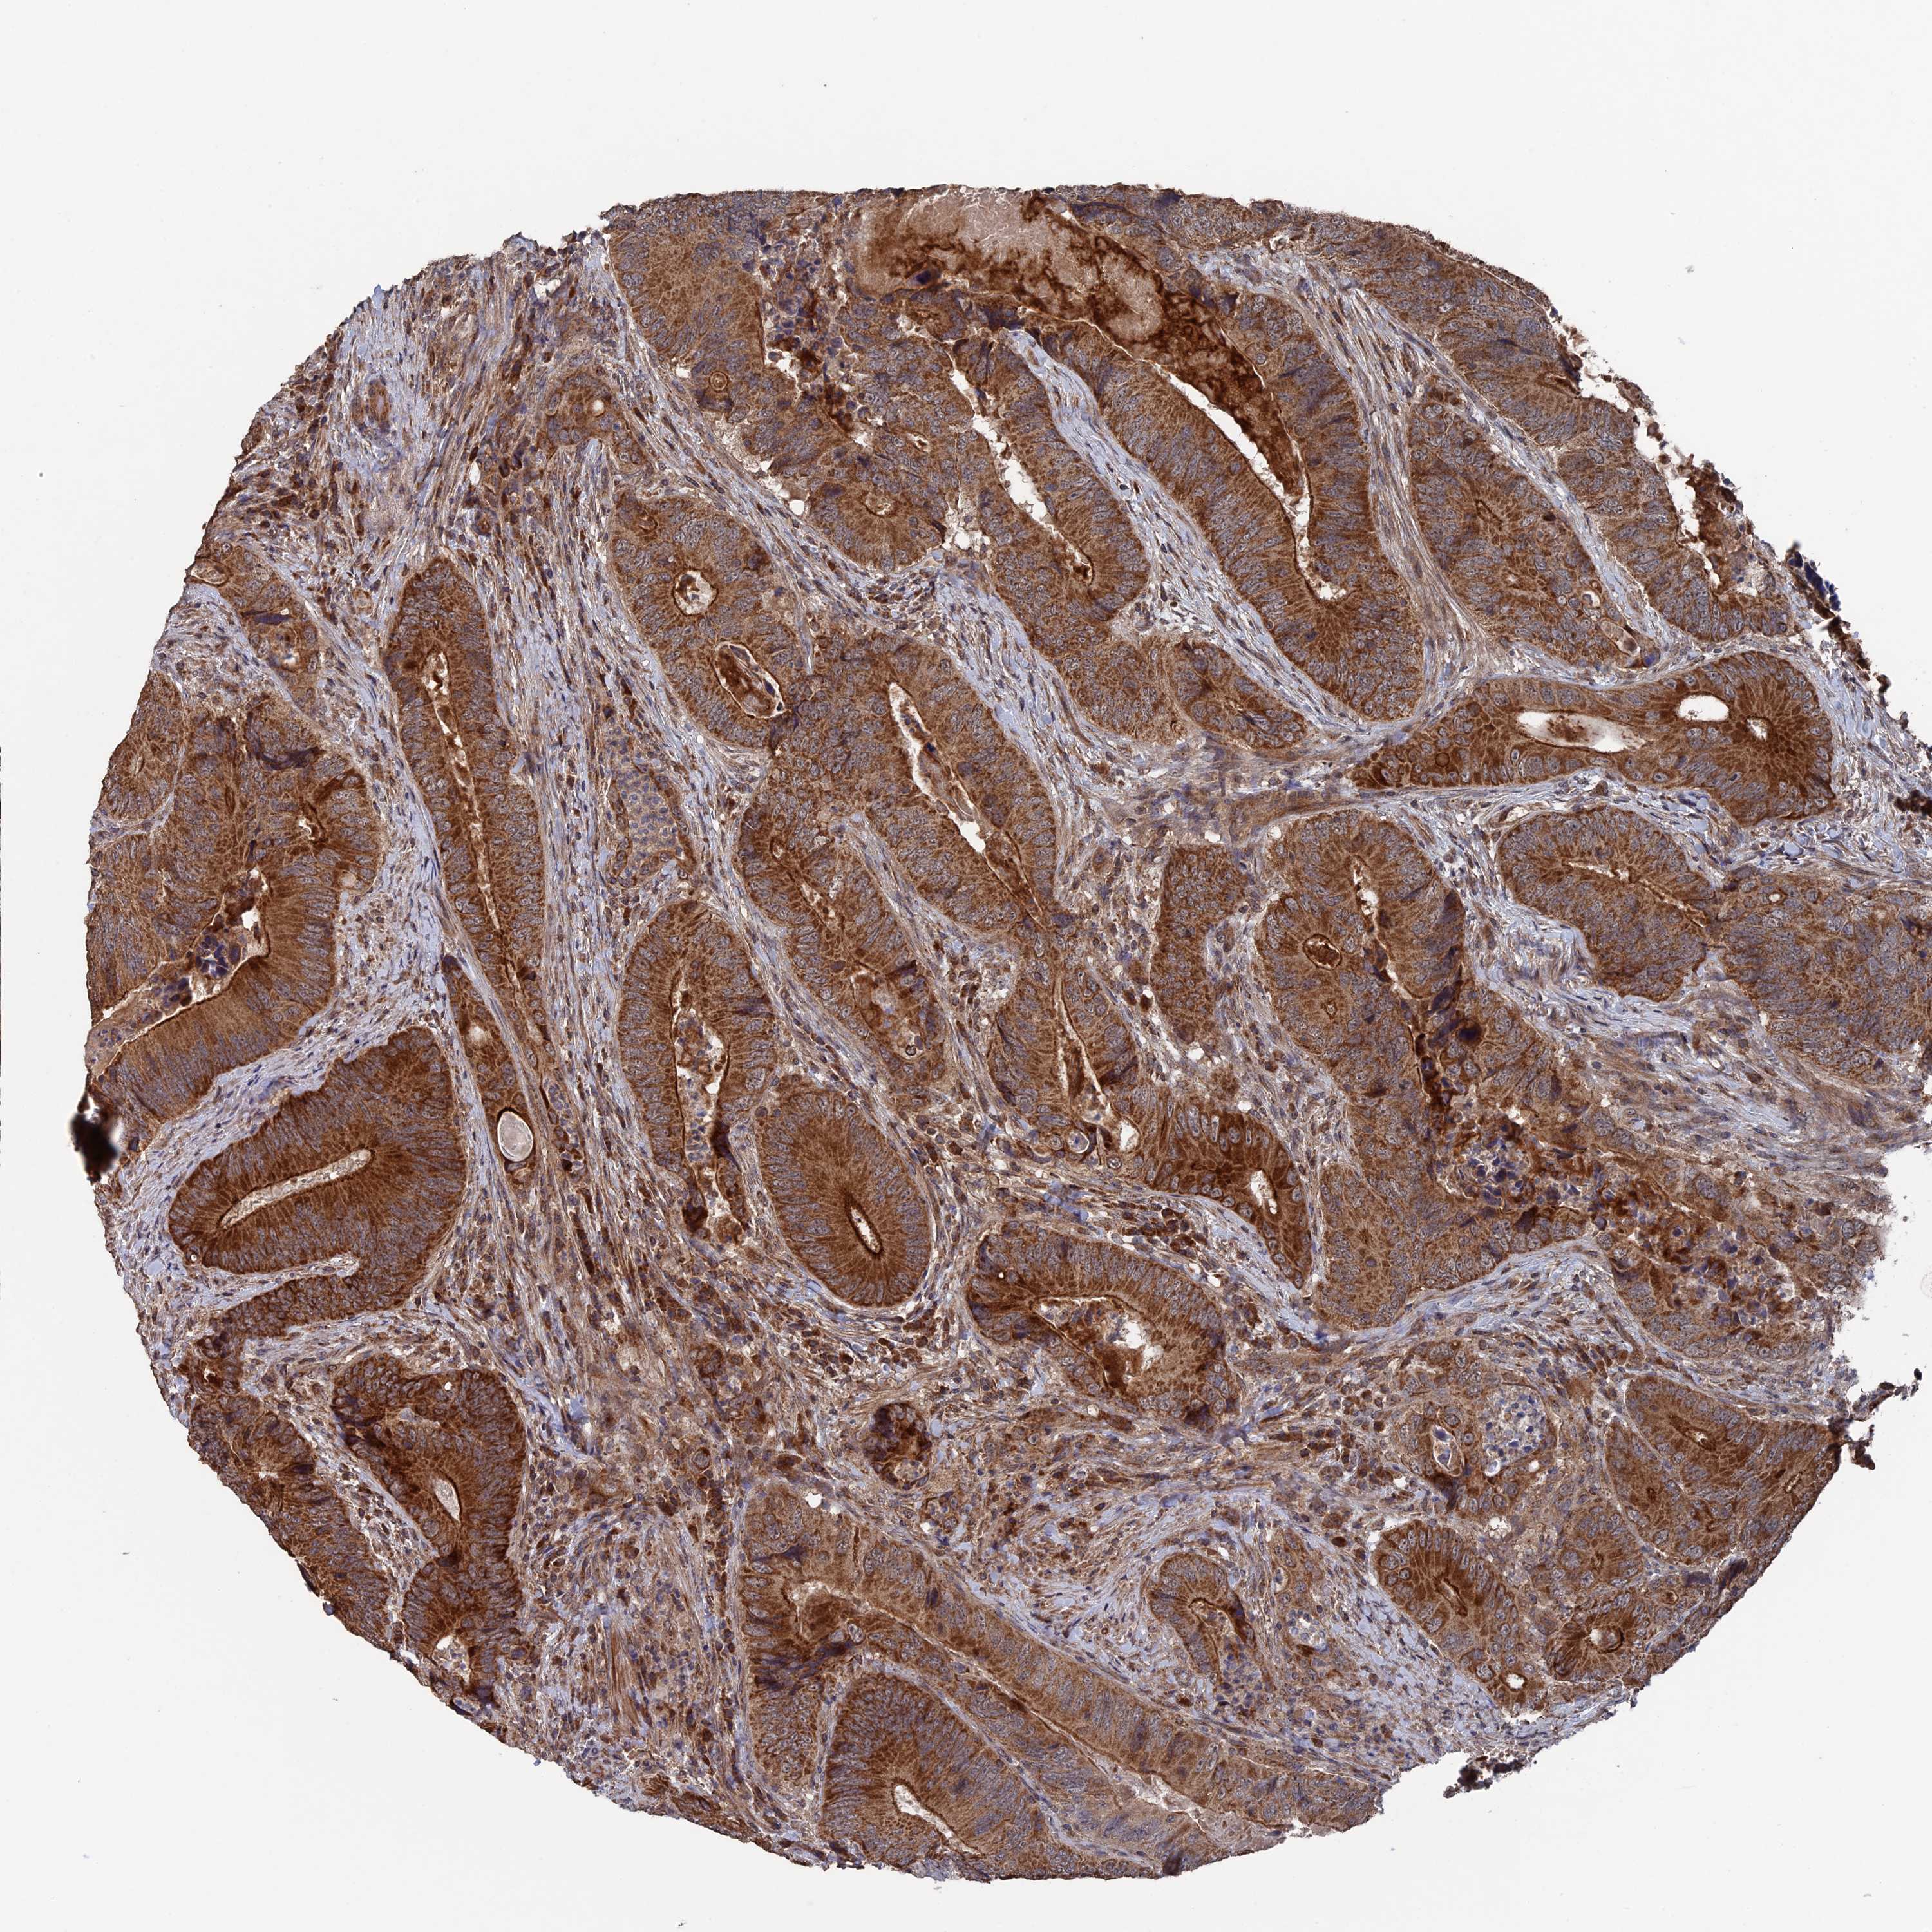

CANCER COLORECTAL CANCER Show tissue menu

Colorectal cancer

Human cancer

Colon adenocarcinoma